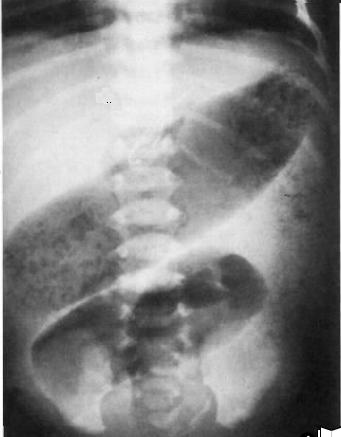

- Aspect radiologique de lavement baryte du

megacolon congenitale de Hirrschprung se monte

que la portion aganglionaire est serre et image de

distension du colon en amont en presence . En

cas de dolicocolon la portion aganglionaire est

etendu le long du colon et aspect du colon dans ce

cas est tres en particuliairement . |

Aspect de

lavement baryte de meme cas : La portion recto-sigmoidienne

innertie ( fleche blanche ) se diminue sa diametre

et la colon ascendent et transverse sont dilate. |

Aspect

radiologique d'une megacolon congenitale (

Hirschprung disease ) . Image de la portion

aganglionaire est tres net sur le cliche OPG (

fleche rouge ) . Sa lumiere est peut serre , lisse ,

mou ( fleche rouge ) . La colon en amont est dilate

, perdre des hautres et la portion en aval est

presque normale . |

Megacolon congenitale

( maladie de Hirschprung ) La colon en amont est

dilate et la portion aganglionaire ( fleche rouge )

est aperitaltisme et serre . La colon rectale en

aval est normale . Lavement baryte du colon , cliche

de face . |

La portion non

innerve du colon

se propulse le bol fecale vers en amont et

la colon se distend . Aspect radiologique lavement

baryte du colon sigmoide . |